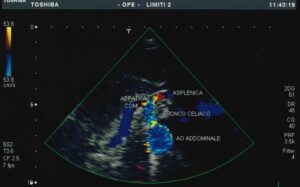

L’esame ecografico dell’aorta addominale ha principalmente lo scopo di identificare per tempo la dilatazione ( aneurisma ) di questa grossa arteria. L’esame consiste nell’appoggiare una sonda ecografica sull’addome, da sotto lo sterno fino all’ombelico, e nella registrazione delle immagini e dei grafici doppler.

L’aneurisma dell’aorta addominale si riscontra nella popolazione adulta con una prevalenza del 5% colpendo maggiormente il sesso maschile con un rapporto di 5:1 rispetto a quello femminile. Viene definito aneurisma una dilatazione dell’aorta che abbia un diametro almeno 1,5 volte superiore al tratto a monte o più semplicemente un diametro maggiore di 3 cm. I fattori predisponenti lo sviluppo di un aneurisma dell’aorta addominale sono l’età, il sesso maschile, l’ipertensione arteriosa, il fumo di sigaretta, il diabete e la presenza della stessa patologia in un parente stretto.

L’esame semplice e privo di radiazioni serve pertanto ad individuare tale patologia, seguirla nel tempo e, quando necessario, porre l’indicazione ad un intervento chirurgico ( aneurismectomia ). Con la metodica in oggetto, in casi selezionati, si può anche verificare la possibilità di un’intervento mediante applicazione di endoprotesi.